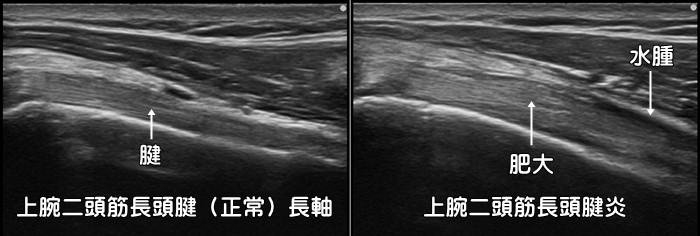

上腕二頭筋長頭腱炎

肩の前方または外側の長引く痛みの原因として上腕二頭筋長頭腱炎・腱鞘炎があります。リレーのバトンを受け取るように後ろへ腕を伸ばすと痛みが増強します。肩だけではなく、上腕の外側や時に前腕から手首にまで痛みが出現します。肩の腱鞘炎ですのでいわゆる使い過ぎ症候群です。炎症反応の動画はこちらで確認できます。